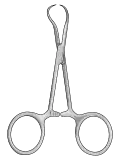

| Needle holder |  |

grasping/holding | Castroviejo Crilewood Mayo-Hegar Olsen-Hegar |